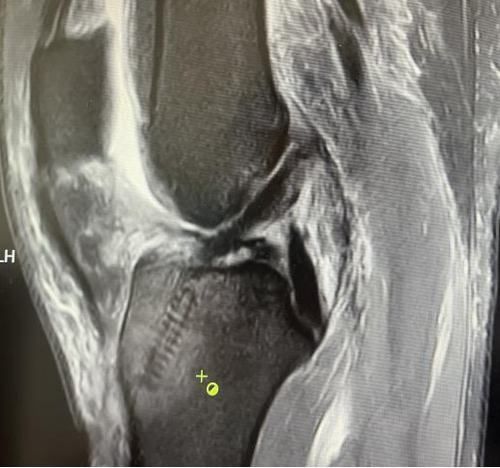

膝關節(jié)韌帶損傷磁共振

我院骨科三病區(qū)近期收治了4名膝關節(jié)交叉韌帶損傷患者。25歲的齊先生,因打籃球時不慎扭傷左膝,致右膝腫痛,遂來我院治療;30歲趙先生酷愛足球,扭傷右膝關節(jié)來我院就診;50歲的張先生、42歲劉先生因騎車滑倒摔傷、膝關節(jié)腫痛不適、活動受限,收治入院。骨科三病區(qū)李鵬主任團隊詳細查體以及完善影像學檢查后進行診斷:幾位患者共同診斷均有“前交叉韌帶損傷”,不同程度合并有“半月板損傷”、“股骨軟骨損傷”、“內(nèi)側副韌帶斷裂”。